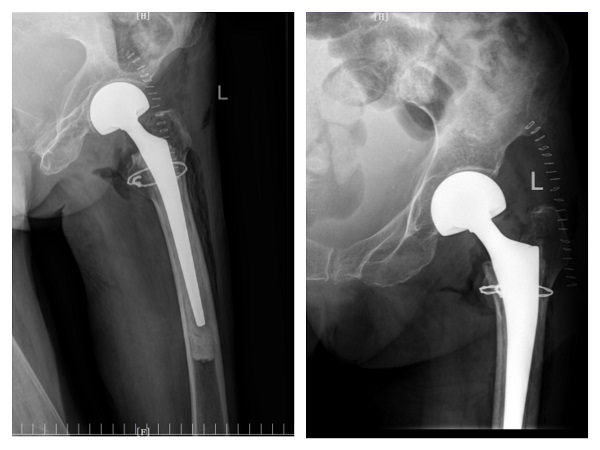

入院一周后,肺部感染逐渐得到控制,氧饱和度正常后,潘主任团队为许爷爷进行左侧人工股骨头置换术,手术十分顺利。术后,科室医护人员密切关注老人的神志、呼吸和各项生命体征变化,及时根据病情变化调整治疗方案,并加强肺功能锻炼。术后三天,许爷爷能够在助行器辅助下下床行走,无明显不适,生命体征平稳。在科室医护团队日夜精心的照料下,许爷爷日见好转,说话声音开始响亮,浑身也有了力气,其家属表示深深地感谢,经过半个多月的精心治疗,许爷爷现已康复出院。